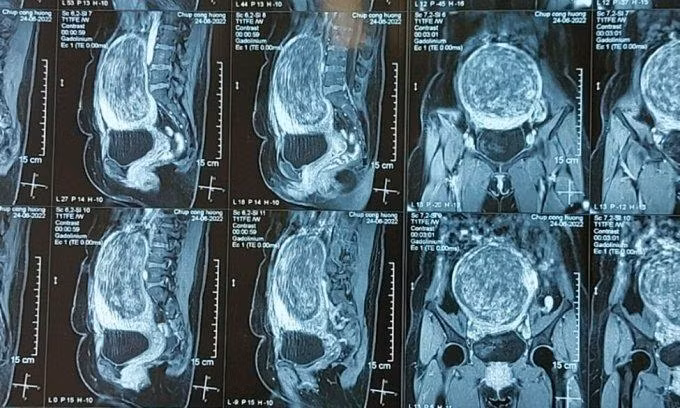

Khối u chèn ép, gây biến dạng nội tạng. Ảnh: BVCC.

BSCKII Nguyễn Thanh Hà - Chủ nhiệm khoa Phụ sản cho biết, khối u xơ quá lớn đã làm biến dạng toàn bộ cấu trúc giải phẫu ở người bệnh.